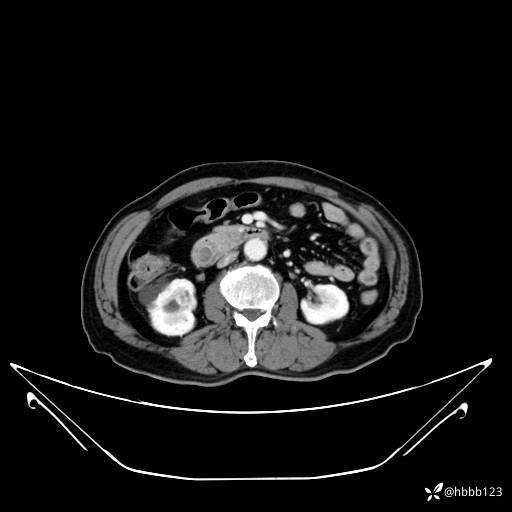

门诊完善上腹部CT平扫+增强扫描:

门脉期: